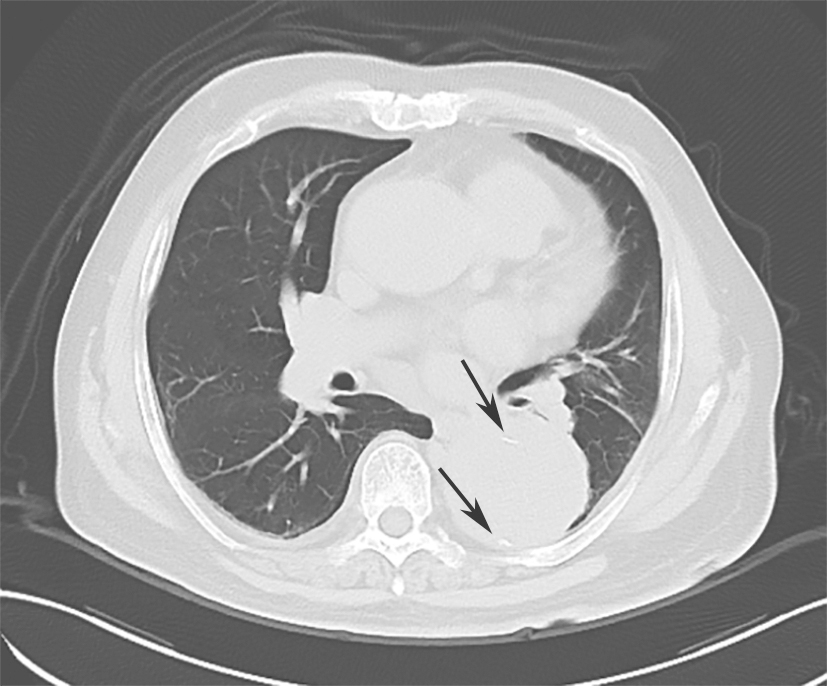

入院后紧急行血管螺旋CT扫描+三维重建,以明确主动脉病变。血管螺旋CT扫描+三维重建如图2所示。降主动脉至腹主动脉夹层动脉瘤并壁间血肿形成(累及主动脉弓至肾动脉开口平面)。升主动脉管径约4.9cm。主动脉弓与降主动脉弥漫管腔增粗,周围可见弥漫壁间血肿形成,向下延伸至肾动脉平面。主动脉弓上三大分支开口与显影良好。主动脉弓外径为5.4cm,内径约3.8cm。降主动脉外径为7.5cm,内径为4.8cm。气管隆嵴下平面降主动脉左前壁局限性钙化上方有一个溃疡,溃疡内有少量对比剂充盈。胸主动脉下段向右侧明显迂曲。腹主动脉与肾动脉平面上方可见内膜片与真假腔形成,假腔内有少量造影剂充填。腹腔干动脉和肠系膜上动脉开口未见受累。右肾动脉开口部分受累,左肾动脉开口未见受累。腹主动脉下段、双侧髂内外动脉血管形态良好。双侧胸腔中等量积(血)液(图3箭头处)。

图3双侧胸腔积(血)液

诊断明确,经血管外科会诊,考虑手术指征明确,完善术前检查后,在全身麻醉下行胸主动脉瘤腔内修复术(thoracic endovascular aneurysm repair,TEVAR),术中植入2枚GORE-TAG支架型血管,覆盖左锁骨下动脉开口至降主动脉折弯处,造影证实瘤体封闭良好。术中行左侧胸腔穿刺引流术。术后给予镇静、抗感染、营养支持等治疗。收缩压维持在100~140mmHg,术后第2天行右侧胸腔穿刺引流术。双侧胸腔共计引流血性积液1830ml。

术后第20天15:20患者出现点头样呼吸,面色苍白,口唇发绀,听诊双肺呼吸音低,以左肺明显。2分钟后心搏骤停,给予持续胸外按压并反复给予药物复苏无效,15:50宣布临床死亡。抢救期间行胸腔超声探查示左侧大量胸腔积液,右侧少量;超声心动图显示,未见心包积液。死亡原因为主动脉夹层动脉瘤破裂。

胸主动脉腔内修复术(thoracic endovascular aortic repair,TEVAR)的主要目的是封闭原发破口,扩张真腔,改善远端脏器、肢体血供,促进假腔血栓化和主动脉重塑。TEVAR适用于锚定区充足(>1.5cm)、非遗传性结缔组织疾病性Stanford B型AD患者。国内荟萃分析结果表明,TEVAR治疗Stanford B型AD的手术成功率为97.66%~99.20%,术后早期患者的死亡比例低(术后30天死亡占2.2%~3.55%),近期疗效良好。IRAD研究表明,与药物治疗相比,TEVAR可提高急性Stanford B型AD患者5年生存率。2014年ESC指南推荐,对于复杂性Stanford B型AD首选腔内治疗;若合并内脏缺血、肢体缺血、疼痛无法控制、主动脉瘤变等严重并发症,需要急诊积极治疗。中国Stanford B型AD患者的平均发病年龄远低于欧美国家,预期寿命长。因此,专家委员会推荐,非复杂性Stanford B型AD患者在最佳药物治疗的基础上首选TEVAR作为进一步治疗措施;另外,TEVAR术中应根据患者病情选择合适类型的覆膜支架,以减小支架远端降主动脉过度扩张或新发破口形成风险。逆行性Stanford A型AD是Stanford B型AD行TEVAR术后最严重的并发症,其发生率为1.4%~10.0%,可能与主动脉壁病变(如合并结缔组织病、急性期主动脉壁水肿等)、术中操作不当、覆膜支架选择不当等因素有关,可发生于术中、术后或随访期,其中约有25%的患者没有症状,仅在复查CTA时发现。该并发症显著增加了患者住院死亡及并发症发生率,一经发现,应按Stanford A型AD治疗原则进行处理。患者在术后20天突发呼吸、心搏骤停,抢救无效死亡,死亡原因考虑为主动脉夹层动脉瘤破裂。该患者临终前病情变化突然,抢救期间行胸腔超声探查示左侧大量胸腔积液,可能为主动脉夹层动脉瘤破裂导致的血性胸腔积液,因患者家属不同意进行尸检,无法获得死亡的直接原因,推测与患者主动脉夹层撕裂范围大、主动脉壁水肿恢复延缓有关。